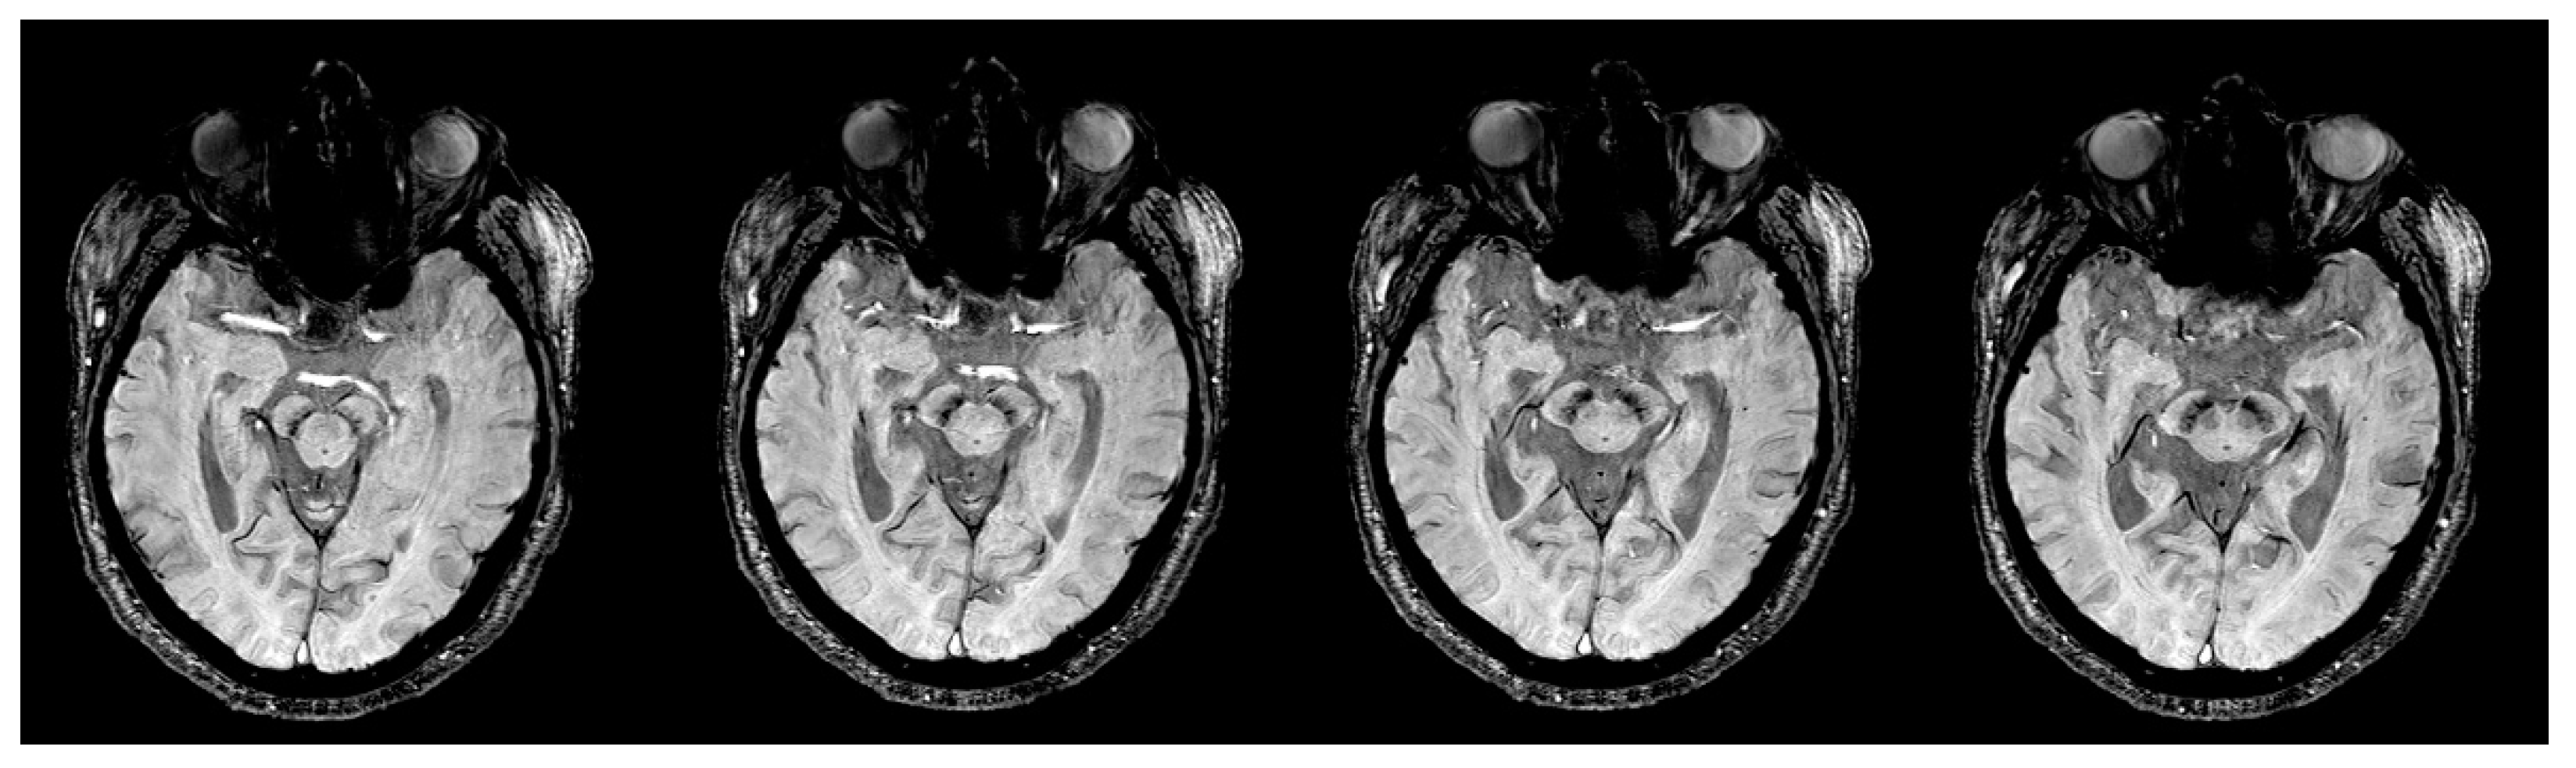

2.2. Imaging Protocols

2.3. Imaging Data Analyses